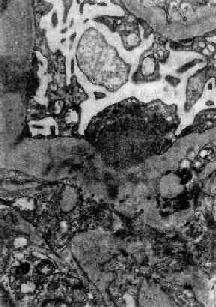

图12-8 毛细血管内增生性肾小球肾炎

电镜下见肾小球毛细血管基底膜表面上皮细胞下有多数驼峰状电子致密沉积物

图12-9 毛细血管内增生性肾小球肾炎

电镜下见驼峰状沉积物位于毛细血管基底膜表面。沉积物表面有上皮细胞覆盖,上皮细胞足突消失